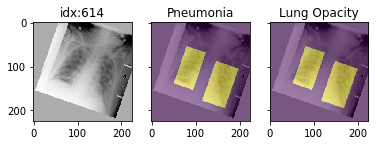

'Support Devices': {0.0: 21757, 1.0: 99747}}Pathology masks (demo notebook)

Masks are available in the following datasets:

xrv.datasets.RSNA_Pneumonia_Dataset() # for Lung Opacity

xrv.datasets.SIIM_Pneumothorax_Dataset() # for Pneumothorax

xrv.datasets.NIH_Dataset() # for Cardiomegaly, Mass, Effusion, ...Example usage:

d_rsna = xrv.datasets.RSNA_Pneumonia_Dataset(imgpath="stage_2_train_images_jpg",

views=["PA","AP"],

pathology_masks=True)

# The has_masks column will let you know if any masks exist for that sample

d_rsna.csv.has_masks.value_counts()

False 20672

True 6012

# Each sample will have a pathology_masks dictionary where the index

# of each pathology will correspond to a mask of that pathology (if it exists).

# There may be more than one mask per sample. But only one per pathology.

sample["pathology_masks"][d_rsna.pathologies.index("Lung Opacity")]it also works with data_augmentation if you pass in data_aug=data_transforms to the dataloader. The random seed is matched to align calls for the image and the mask.